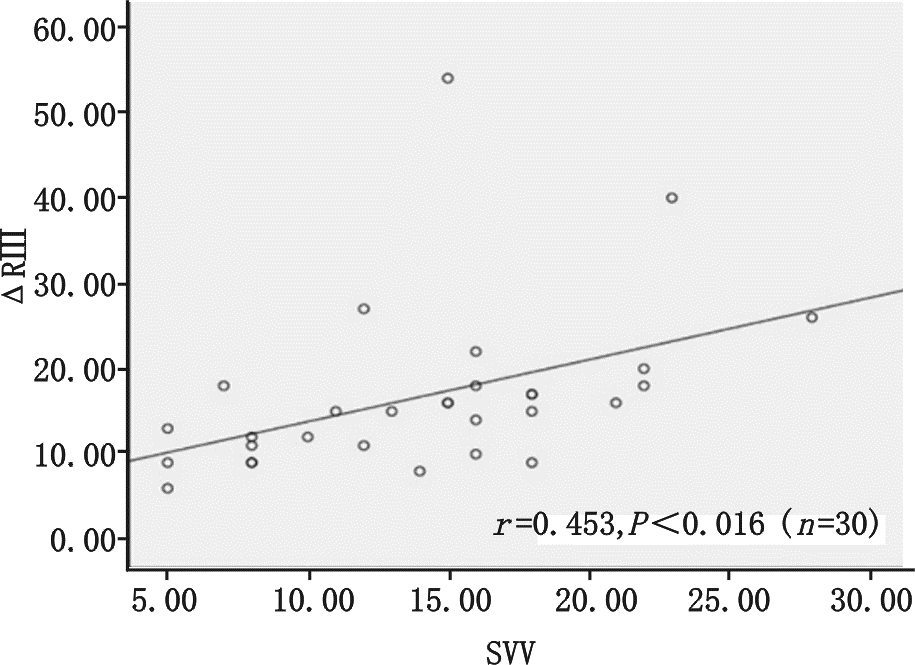

图 1显示ΔRⅡ随着呼吸周期显著的周期性变化,观察研究发现呼吸周期性ΔRⅡ与SVV呈正相关性(r=0.807,P<0.01见图 2),而呼吸周期性ΔR Ⅲ、ΔR AVF与SVV的相关性分别为(r= 0.453,P=0.016,r=0.642 ,P<0.01,分别见图 3、4);

| 图 3 呼吸周期性ΔR Ⅲ与每搏量变异的相关性 |

机械通气患者,吸气相胸腔内正压增大,导致右心回流减少,同时右心后负荷增加,致右心每搏量减少,经过两三个心动周期后左心室的前负荷减少,就这样左心室的每搏量随着呼吸周期波动,在吸气末每搏量达最大值,呼气末每搏量为最小值,这种现象在心脏Staring 曲线的上升支更明显,在平坦支就不明显,所以这种变异是反应心脏前负荷的指标[4, 13]。心电图R波幅度随呼吸周期性变化的理论基础是“Brody 效应”[7],即心脏内血液的电阻比心肌组织低,心脏内血液越多电阻越小,传导至身体皮肤表面的电量越大。基于心肺交互原理,机械通气吸气相正压通气挤压肺血管床使左室前负荷增加,左室容积增加,故在吸气末左室前负荷最大即左室容量最大,此时R波波幅最大,每搏量也最大,而呼气末R波波幅最小,每搏量也最小。实际上R波波幅从原理上代表的是心室内的血容量,每搏量是代表着从心室射到主动脉的血容量,两者是同源的,所以心电图呼吸周期性R波波幅变化与每搏量变异相关,且能反应血管内容量。研究表明V5、V6的R波受左室在胸腔内位置影响较大,而Ⅱ、Ⅲ、AVF导联R波基本不受影响[14, 15],故本研究选择ΔRⅡ、ΔR Ⅲ、ΔR AVF为研究对象,结果显示ΔRⅡ、ΔR Ⅲ、ΔR AVF与SVV相关,而且我们发现ΔRⅡ与SVV相关性最好,明显优于ΔR Ⅲ、ΔR AVF,与先前研究结果一致[14],这可能与Ⅱ 导联与正常心脏电轴最接近的原因相关。大量研究表明SVV ≥12%为预测容量反应性的阈值[5],本研究比较SVV≥12%组与SVV < 12%组的HR、CVP 、MAP、CI,均显示差异无统计学意义,但全心舒张末期容积指数(GEDVI)两组间差异具有统计学意义,说明预测容量方面GEDVI优于HR、CVP 、MAP、CI,但其监测需行PICCO,费用昂贵,且操作不便。笔者通过受试者工作特征(ROC)曲线评估ΔRⅡ预测SVV≥12%能力,其曲线下面积(AUC)为0.910±0.055(P<0.01),与PPV预测SVV差异无统计学意义。以ΔRⅡ临界值为11.5%预测SVV≥12%,其敏感度80%,特异度90%,说明在感染性休克机械通气的患者ΔRⅡ能准确反应或预测SVV值,虽然本实验未行容量负荷试验,但这给我们启示是否ΔRⅡ可作为SVV替代指标应用于机械通气患者辅助评估容量反应性,待进一步研究证明,进而开发应用ΔRⅡ这个新指标在心电监护仪上持续监测,如同PPV一样。